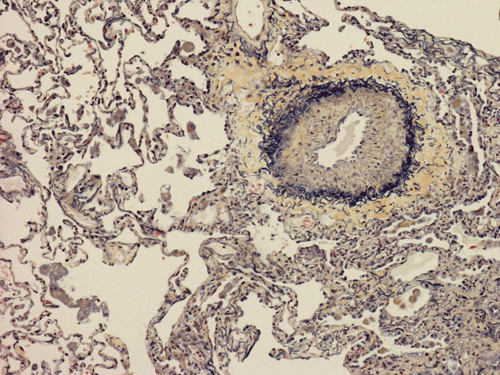

At scanning magnification (Panel A), the lung parenchyma is replaced by some coalescing fibrous nodules. The degree of involvement is variable at different fragments (Panel B and C). In the less affected areas, there are some fibrotic thickening of the septa (Panel C). In some areas, the changes are minimal and the pleural appear to be uninvolved (Panel D and E). In low to medium magnifications, these nodules of fibrosis contains a large number of hemosiderin laden macrophages (Panel F and G) admixed with fibrous tissue. The diagnostic tissue, however, is present in areas with increased cellularity. In these areas, there is a background of cells with a moderate amount of cytoplasm and bland nuclei. Some of these nuclei have kidney shape (arrow in Panel H). In some areas, many of the nuclei have a deep nuclear groove that resemble a coffee bean (arrow in Panel I). In the third type of areas, the nuclear grooving is not distinct (Panel J). Prominent eosinophilic infiltrations are almost always present. Immunohistochemistry on CD1a revealed many positive cells (Panel L). Also present in the specimen are multiple small blood vessels with thickened intima (Panel K). A Movat pentachrome stain demonstrates an internal elastic layer in these vessels and confirms that these are arteries (Panel M and N).

In the end stage, the exhausted lesions are predominantly fibrotic and largely depleted of LCs. In some regions, the fibrosis may surround cystic spaces of variable diameter to form large areas of honeycombing. This is especially predominant in the upper lobes. In cases where parenchymal scaring is present, the pulmonary function will be largely compromised. At this stage, both pulmonary function tests and radiologic findings may suggest diffuse lung disease, but biopsy will show stellate fibrotic lesions centered on the terminal airways with no identifiable interstitial inflammation. Pulmonary vasculopathy (in areas of lung remote from parenchymal nodules) is also seen in late stage PLCH. Vasculopathy manifests as intimal fibrosis, medial hypertrophy or luminal obliteration involving both venules and arteries. This may account for pulmonary hypertension seen late in PLCH.

Silverman-Movat Pentachrome is a stain that utilizesfive different stain components (orcein, alcian blue, woodstain scarlet, acid fuchsin and Spanish saffron) to aid in the visualization of elastic fibers, mucin and collagen. Orcein allows visualization of elastic fibers in acid-alcohol solution and colors them purple to black. Alcian blue stains acid mucopolysaccharides/mucin blue. Both woodstain scarlet and acid fuchsin are used in combination to stain muscle fibers red with longitudinal myofibrils, cross striations and intercalated discs delineated. Spanish saffron colors connective tissue yellow to yellow-green.

In this case it was utilized for two purposes. Since usual interstitial pulmonary fibrosis was one of the differential diagnosis, this stain can be used to demonstrate coexisting old and young/cellular fibrosis. Old fibrosis would appear yellow and the young fibrosis would appear blue-green (ground substance). It proved to be negative. The second purpose (not originally intended) was to help emphasize the thickened intimal layer seen with the associated vasculopathy.